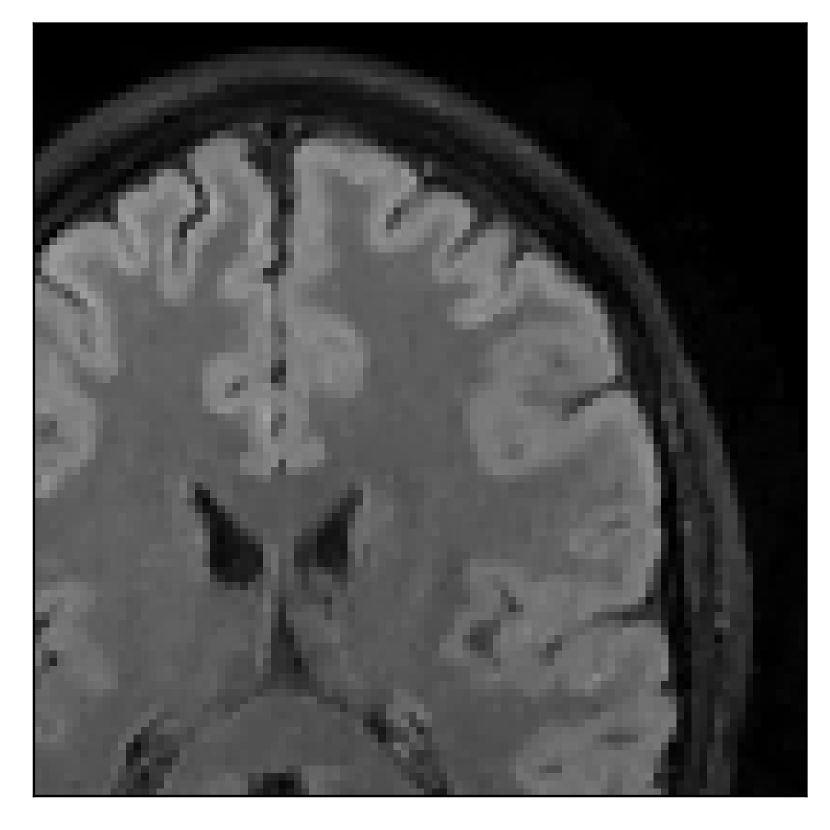

4.2 Experiment 2: choice of the reference contrast

With the experiment described in Section 3.2, we demonstrate the flexibility of the correction scheme with respect to the choice of the reference contrast. The results are shown in Figure 10. Contrary to the experiments detailed in the previous section, we are now considering a T2-weighted reference contrast to guide the correction of a T1-weighted corrupted contrast. The quality of the correction indicates that the proposed technique is rather flexible in terms of reference contrast.

| Section 3.2, Figure 10 | Sagittal | 25.84 | 28.07 | 0.7032 | 0.8093 |

| Coronal | 26.35 | 30.40 | 0.7851 | 0.9021 | |

| Axial | 28.11 | 30.54 | 0.8248 | 0.9012 | |

| Section 3.2, Figure 10 | T1 | Completely corrected | Some blurring | No additional artifacts | Good grey white matter differentiation, |

| some loss of grey matter low signal | |||||